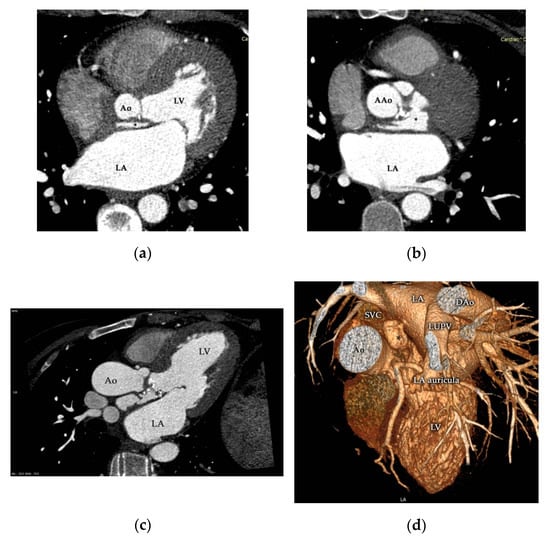

Native Aortic Valve Endocarditis Complicated by Splenic Infarction and Giant Mitral-Aortic Intervalvular Fibrosa Pseudoaneurysm—A Case Report and Brief Review of the Literature

2. Case Presentation